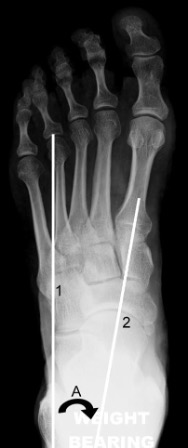

Dorsoplantar view

Line 1 = longitudinal axis of hindfoot

Line 2 = midline axis of talus

A = talocalcaneal angle

Longitudinal axis of the hindfoot

A line parallel to the distal lateral border of the calcaneus.

Normal: parallel to the long axis of the fourth metatarsal.

Talo-calcaneal angle

Measured between the longitudinal axis of the hindfoot and a line along the midline axis of the talus.

Normal: 15-35°